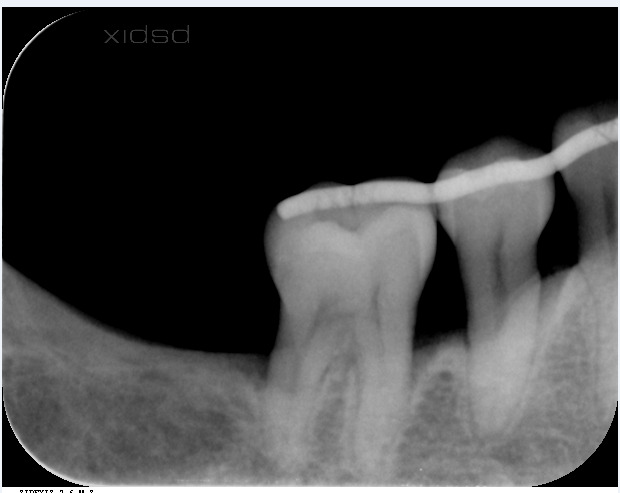

術後1年でここまで回復

勿論、歯茎も切っていません、再生材料も一切使用しておりません。